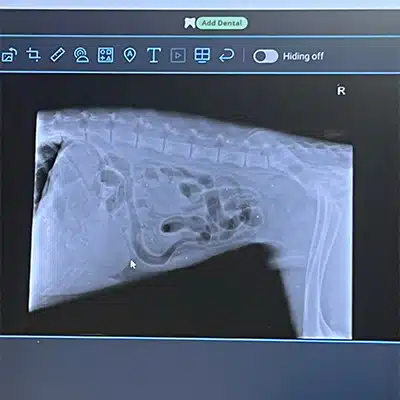

Knowing our girl, we had faith Kaya could make the trip, and sure enough, she was strong-willed enough to reach the vet! Once she arrived, they quickly tried to diagnose her, but the x-rays just weren’t providing enough information. The vets believed it was either intestinal torsion or gastric torsion, which is when the stomach begins to twist, and is the end stages of bloat. We were hoping for the latter, as our vet informed us that 75% of animals who have intestinal torsion are euthanized.

Luckily, when the vet began surgery, they were able to confirm that Kaya was in gastric torsion, with a stomach that was twisted 270 degrees. Though gastric torsion is no walk in the park either, the vet did state that this prognosis dramatically increased her post-surgery success rate! Thus, we proceed with the surgery and hoped for Kaya to pull through.